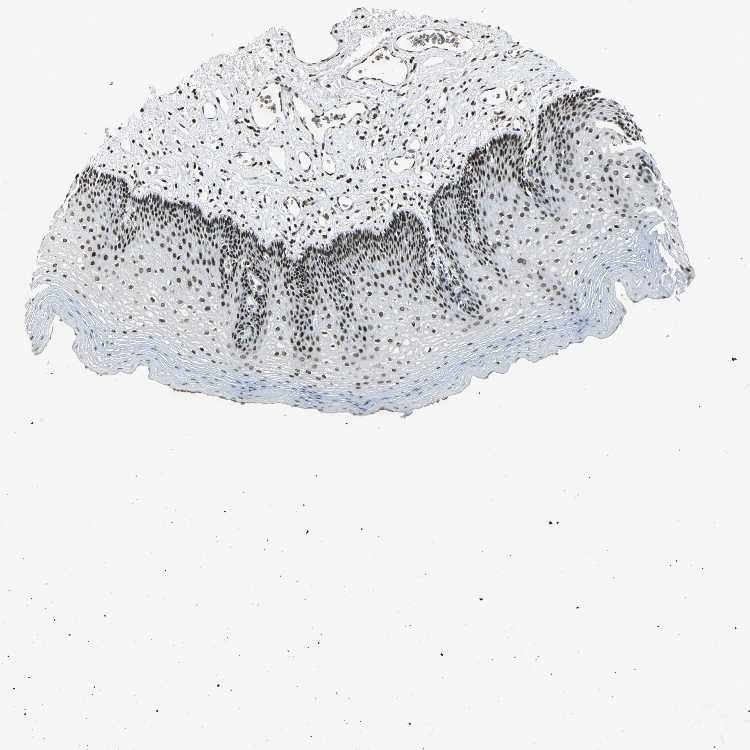

TISSUE PRIMARY DATA ESOPHAGUS Show tissue menu

Esophagus

ESOPHAGUS - Expression summary

Protein expression

Esophagusi

On the top, protein expression in current human tissue, based on all annotated cell types, is reported with the units not detected (n), low (l), medium (m) and high (h). Underneath, protein expression in each annotated cell type are reported using the same units.

Protein expression data is based on knowledge-based annotation. For genes where more than one antibody has been used, a collective score is set.

If knowledge-based annotation could not be performed for a gene, no data is displayed here. View antibody staining data further down this page.

Squamous epithelial cells: High

ESOPHAGUS - Antibody stainingi

Antibody staining in the annotated cell types in the current human tissue is reported as not detected, low, medium, or high, based on conventional immunohistochemistry profiling in selected tissues. This score is based on the combination of the staining intensity and fraction of stained cells.

Each image is clickable and will lead to virtual microscopy that enables deeper exploration of all samples and also displays staining intensity scores, fraction scores and subcellular localization as well as patient and tissue information for each sample.

Antibody HPA006195Antibody HPA006474

Squamous epithelial cells HighHigh